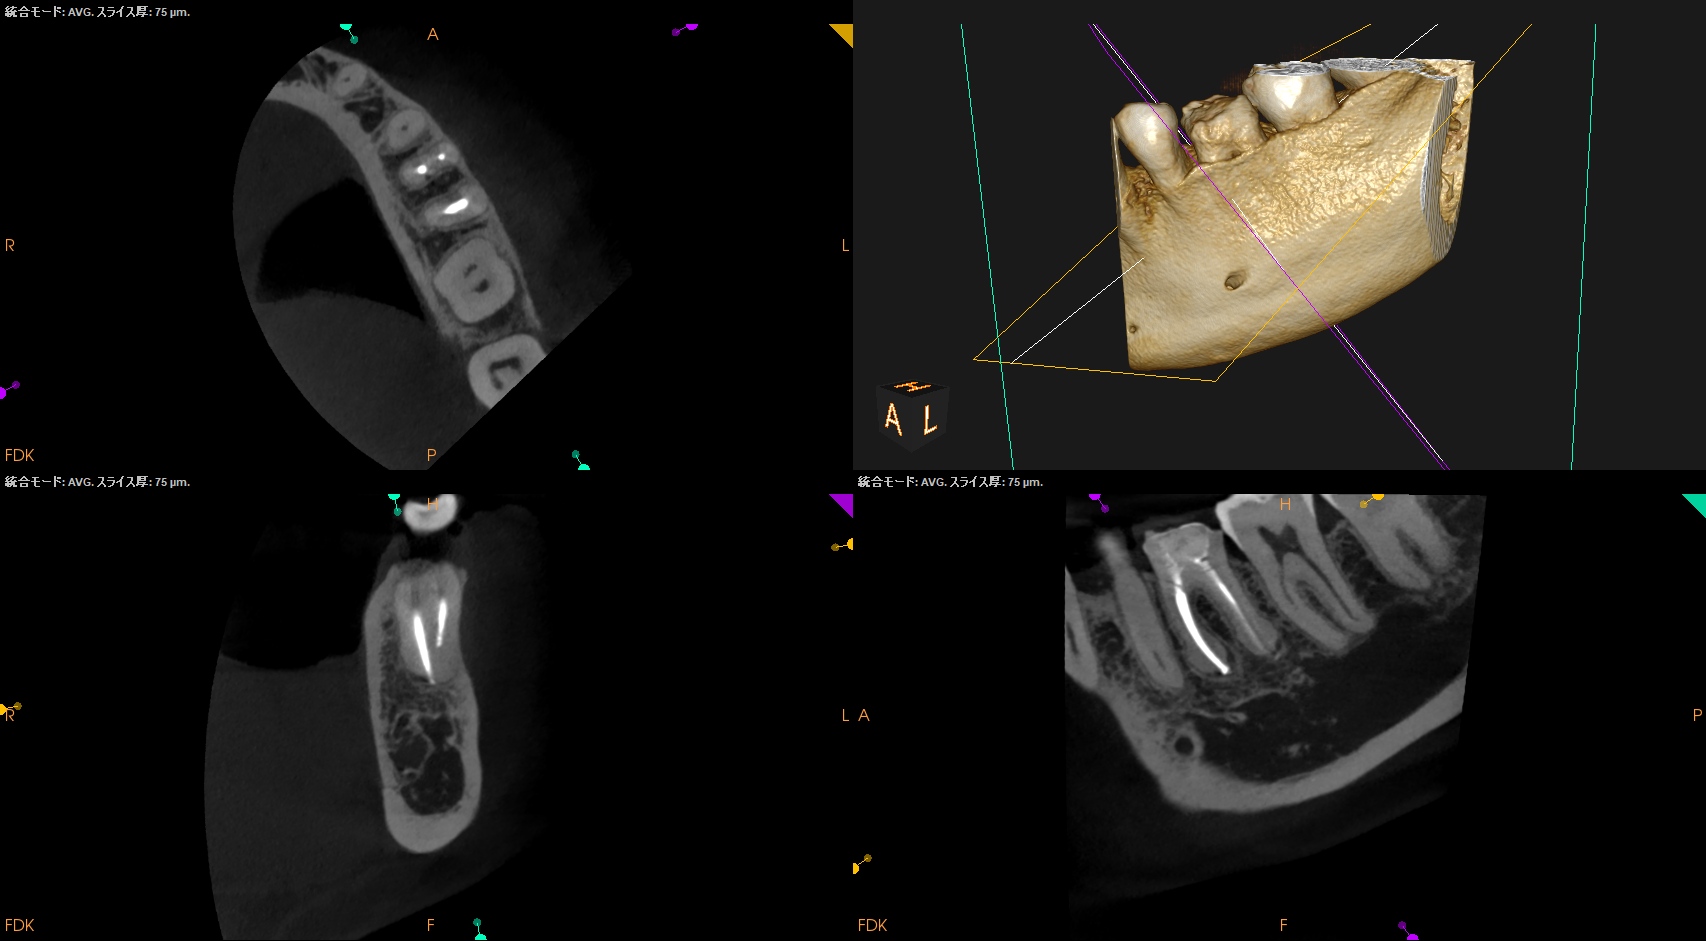

昨日の記事の経過観察。

治療から1年が経過していた。

臨床症状は1年経過してもないそうだ。

画像的にはどうだろうか?

初診時と比較した。

大きく問題が解決していることがわかるだろう。

ファイルが折れたMBも、

Overextensionした?ML,Dも、

根尖病変が消失している。

これはひとえに、

ルールを遵守した歯内療法の成果であるといえよう。

経過観察もこの日で終診とさせていただいた。